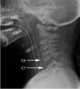

Cervical spine injury

A spinal cord injury (SCI) is damage to the spinal cord that causes temporary or permanent changes in its function. Symptoms may include loss of muscle function, sensation, or autonomic function in the parts of the body served by the spinal cord below the level of the injury. [Source: Wikipedia ]